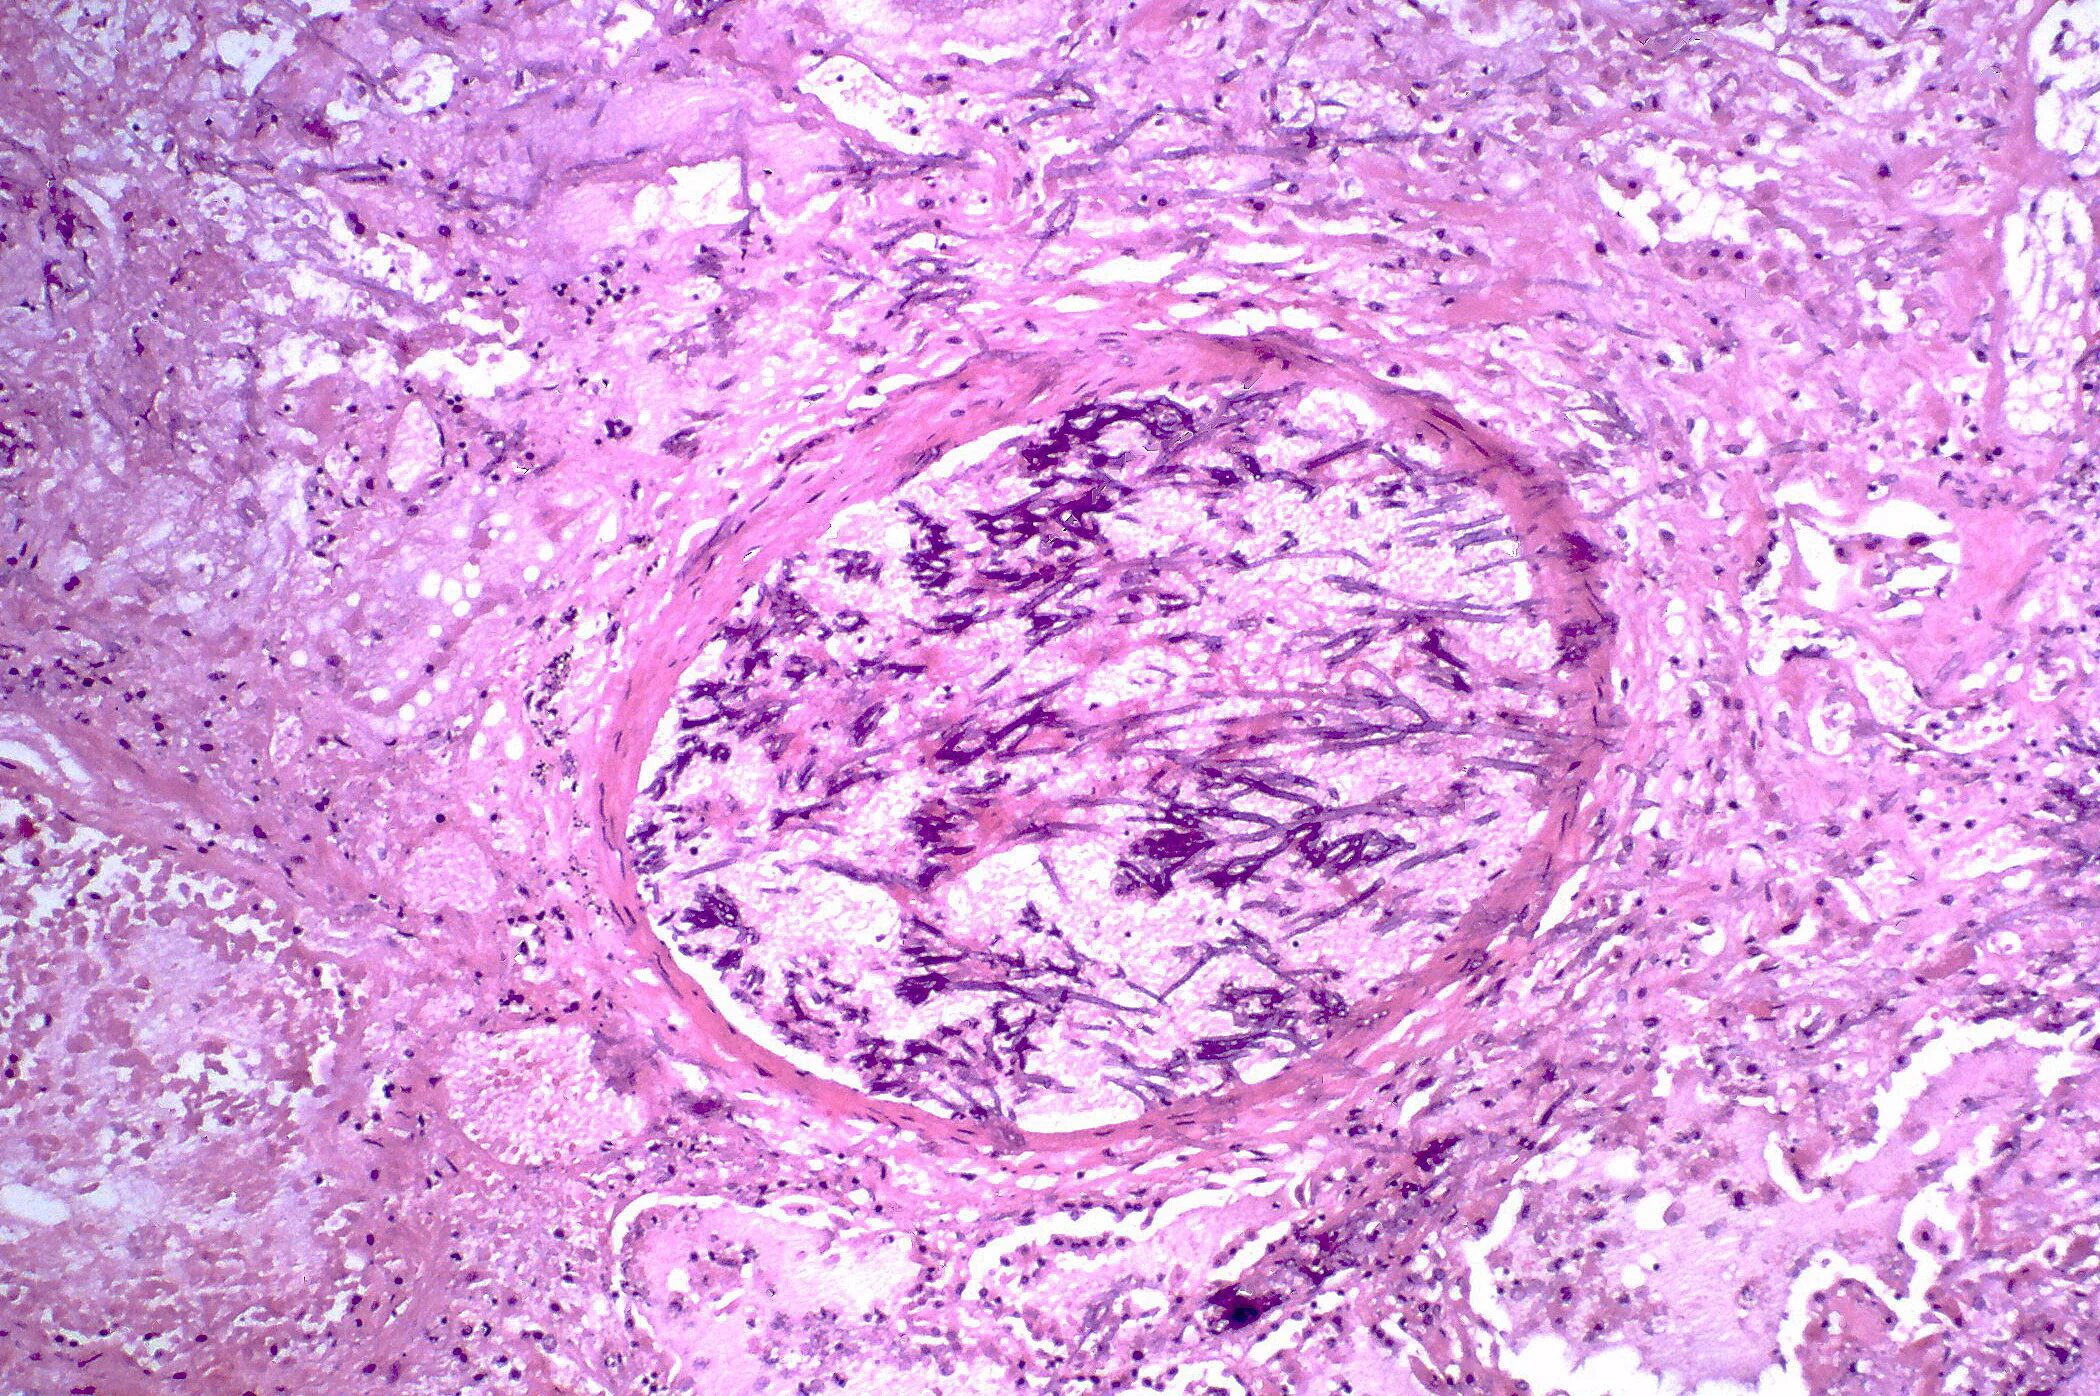

Патанат